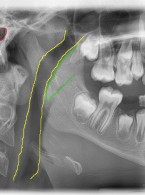

Dekoronacja

jako postępowanie zalecane w leczeniu pacjentów z postępującą pourazową infrapozycją zębów siecznych szczęki